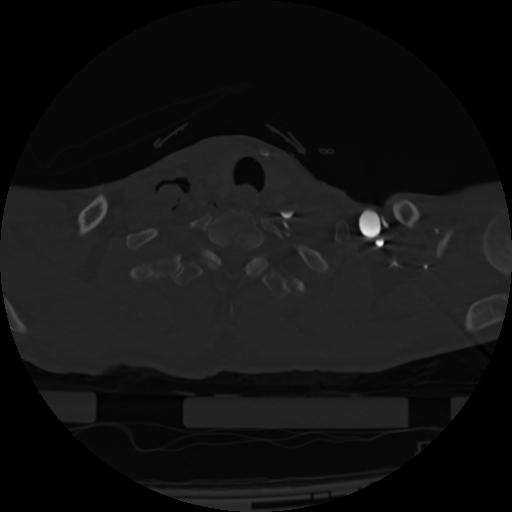

22 ANGIO,CE,Vol,0.5,ANGIO,,